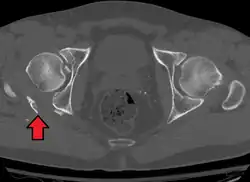

Axial CT image (viewed on bone windows) of a complex comminuted left acetabular fracture involving both anterior and posterior columns. -

In all cases, CT scan can assist in identifying impacted bone pieces, which may be found within the joint, and MRI may be done to identify the extent of potential injury to the sciatic nerve.